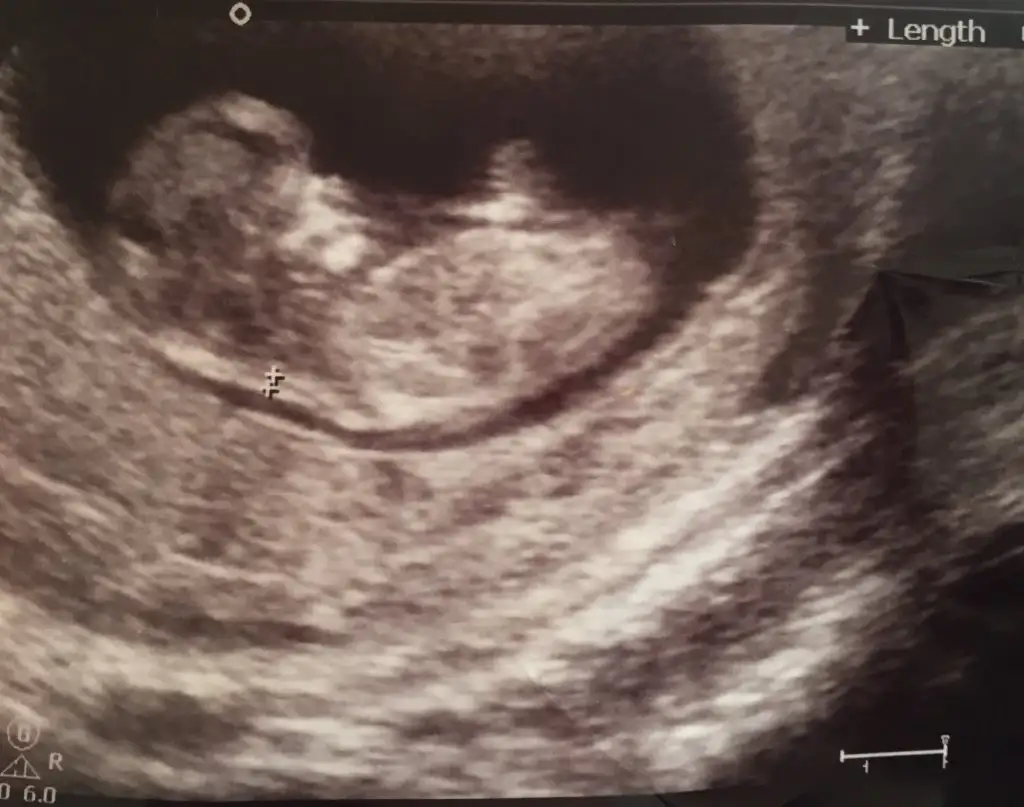

kızlar 12 haftalık...

doktor birdahakı ay bakalım yanılma çok oluyor dedi....sizce ?

SiZce Kız Mı Erkek mi hanımlar??

Nub için paralel kıza benziyo dedi ama kesin bişey demedi..2 oğlum var çok kız istiyorum bakalım nasip:)